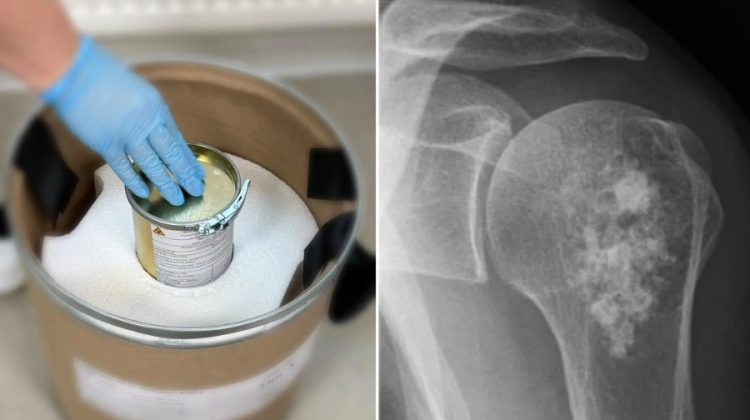

El medicamento Rakurs actúa directamente sobre los tumores en los huesos para mejorar la salud de los pacientes

Rusia ha comenzado a usar un fármaco llamado Rakurs, creado para atacar el cáncer de forma más precisa. El medicamento ya pasó todas las pruebas legales y los primeros lotes llegaron a los hospitales para ser aplicados en pacientes que lo necesitan.

Este fármaco es especial porque usa una técnica de radiación dirigida que ataca directamente los tumores que se han extendido a los huesos. Su función principal es destruir las células enfermas con exactitud, lo que ayuda a calmar el dolor y permite que los pacientes se sientan mucho mejor durante su tratamiento.